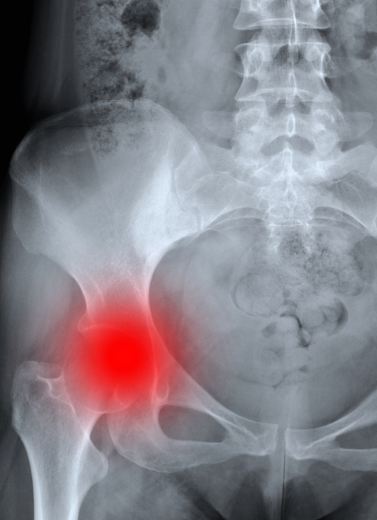

Arthritis and rheumatologic diseases can severely aect your quality of life with persistent pain, swelling, and limited movement. At our Rheumatology & Arthritis Department, Dr. Anand Bhushan oers comprehensive diagnosis and tailored treatments that control symptoms, slow disease progression, and improve joint function.

Osteoarthritis (Wear-and-Tear Arthritis)